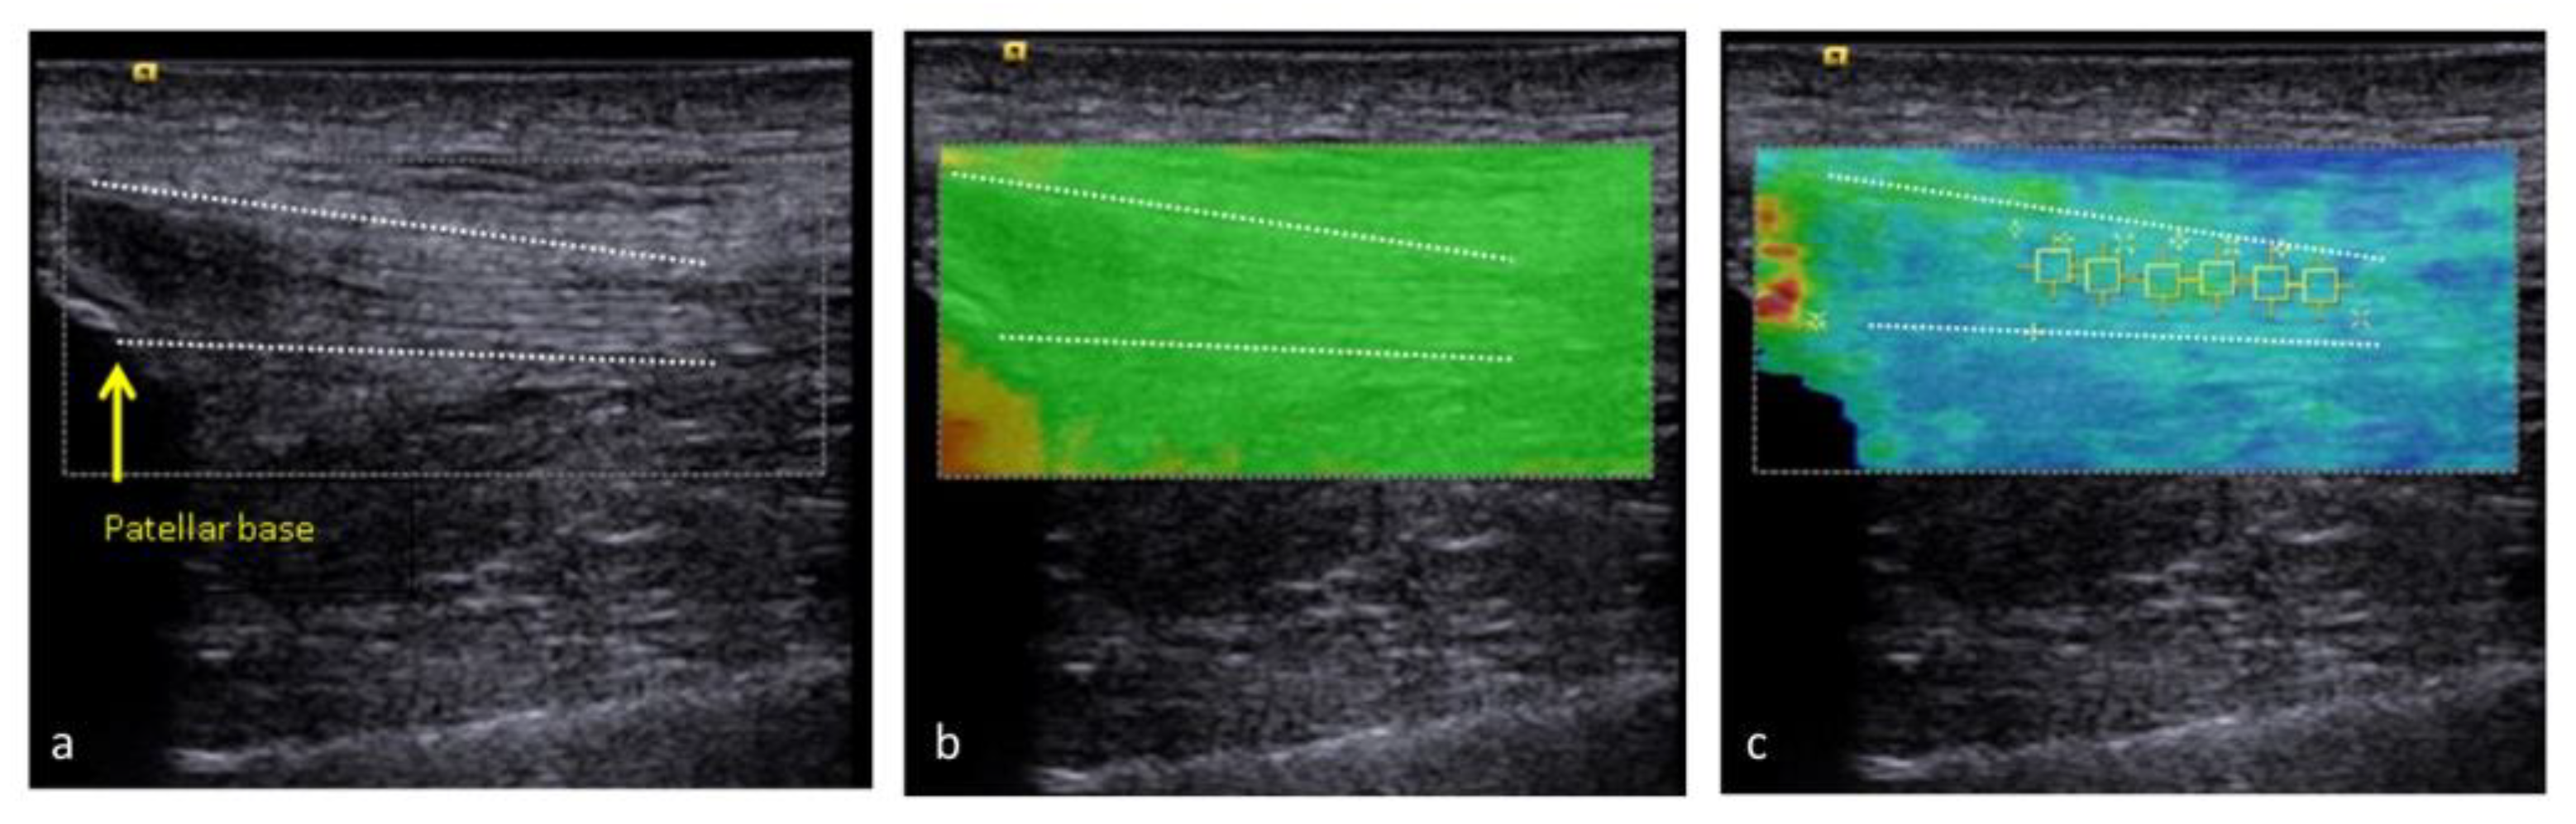

2.3. Ultrasound Examination Protocol